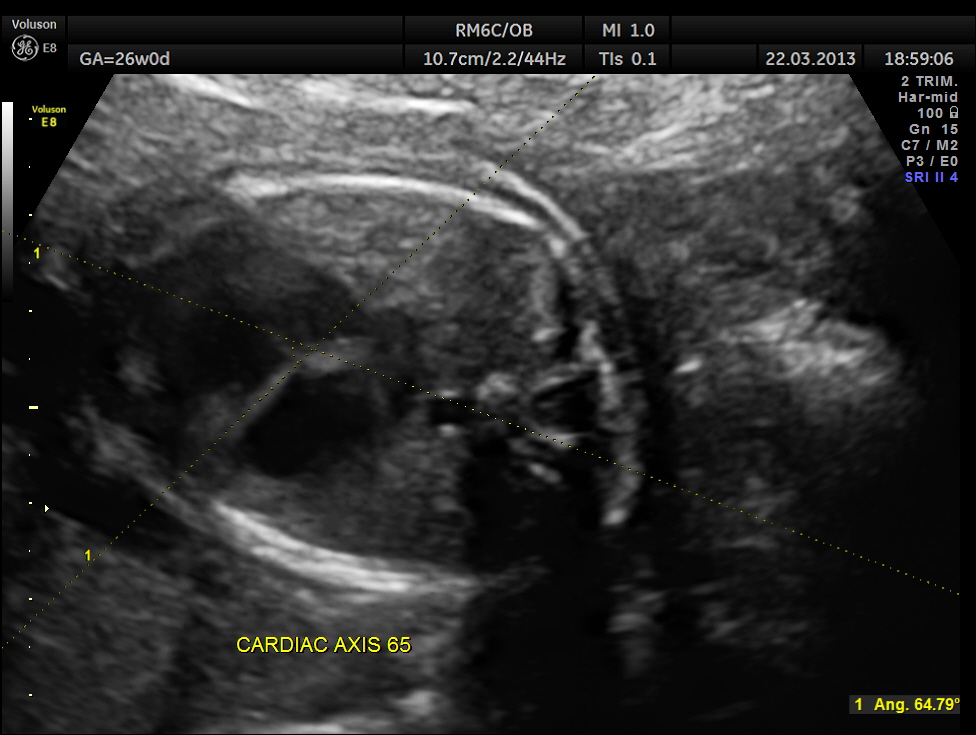

cardiac axis of less than 29 or more than 59 is considered abnormal ; in this fetus it was 65

5. Abnormal cardiac axis